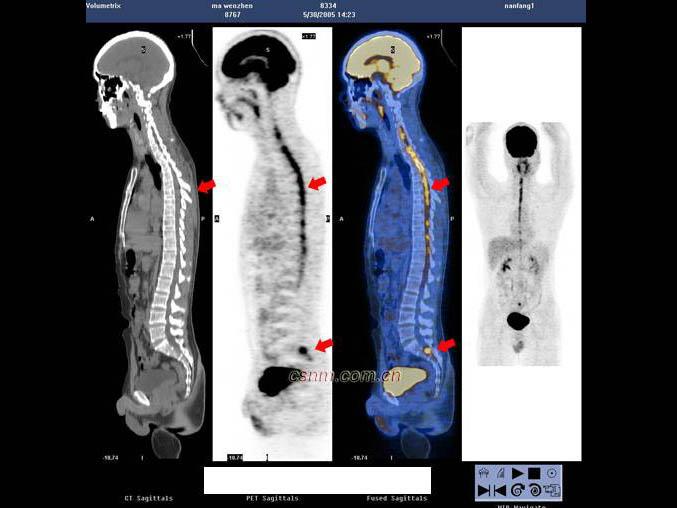

男,7岁,2岁时因头痛而就诊,MRI示脑积水、颅内(小脑蚓部及蝶鞍)见多发恶性肿瘤,临床诊断为髓母细胞瘤。未行手术治疗,多年来一直行放、化疗治疗,最后一次化疗1个月前结束。因腹胀、恶心、呕吐1周而就诊,CT示:双侧侧脑室充满肿瘤病灶,PET/CT全身显像如图。正确的描述是 ( )

A.肿瘤复发并沿双侧侧脑室弥漫性浸润

B.肿瘤同时向双侧丘脑及豆状核浸润、侵犯;蝶鞍内块状高代谢病灶,考虑为转移灶